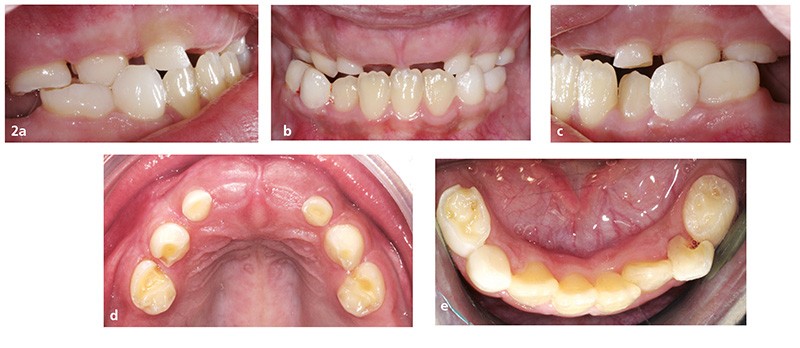

L’examen endo-buccal (fig. 2a à e) montre, au maxillaire, la présence des incisives latérales, canines et premières molaires temporaires (les incisives centrales étant tombées depuis la réalisation de la radiographie panoramique) et l’absence de toutes les dents permanentes et des deuxièmes molaires temporaires. À la mandibule, les quatre incisives permanentes ont évolué et il persiste les canines et les premières molaires temporaires. Aucune autre dent n’est visible dans la cavité buccale.

Les relations occlusales sagittales sont subnormales, mais on constate une insuffisance transversale de l’arcade maxillaire…